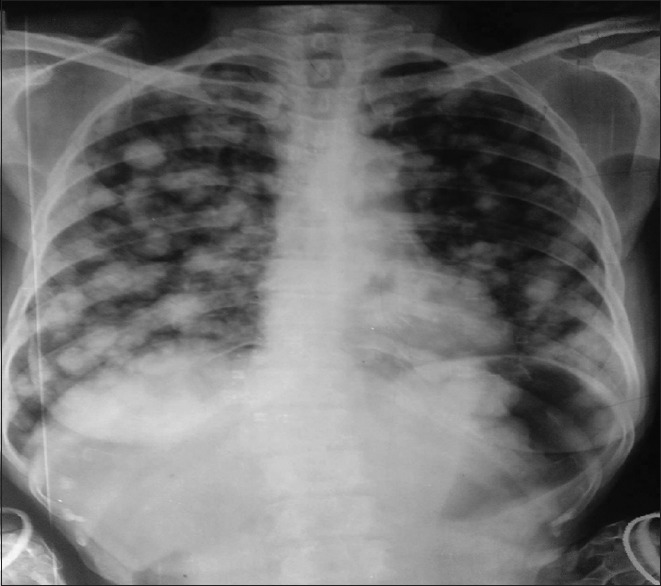

A chest X-ray, posterior-anterior (PA) view, revealed multiple pulmonary nodules, which were highly suggestive of malignancy [Figure 1]. A contrast-enhanced computed tomography (CT) scan of chest revealed ‘cannon-ball’ pulmonary metastases [Figure 2]. Ultrasonography (USG) of the abdomen revealed thickened gastric cardia and fundic areas, with multiple enlarged perigastric and pericoeliac lymph nodes. Contrast-enhanced computed tomography (CECT) of the abdomen was ordered, to look for an abdominal source of metastases. It confirmed the sonographic findings [Figure 3]. A Barium Meal X-ray revealed ‘cannon-ball’ pulmonary metastases, with free flow of dye in the stomach [Figure 4]. Upper gastrointestinal (GI) endoscopy with a guided biopsy was ordered. The histopathological examination (HPE) revealed a well-differentiated adenocarcinoma of the stomach [Figure 5]. However, the patient decided not to undergo treatment and chose hospice and palliative care at her home.

Figure 1.

Chest X-ray showing cannon-ball pulmonary metastases